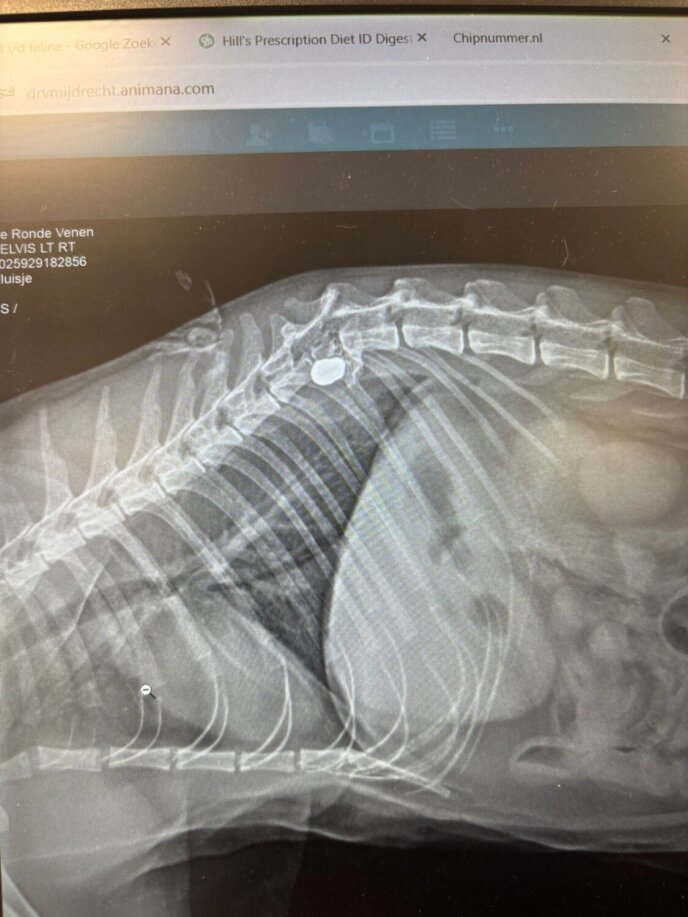

Met spoed ging het dier naar de dierenarts. Na onderzoek kwam de dierenarts met tranen in haar ogen teruglopen: een kogel had een ruggenwervel geraakt. “Je buik draait twee keer om. Wat is dit nou weer,” zegt Cornee. Er was geen andere keuze dan Pluisje in te laten slapen.